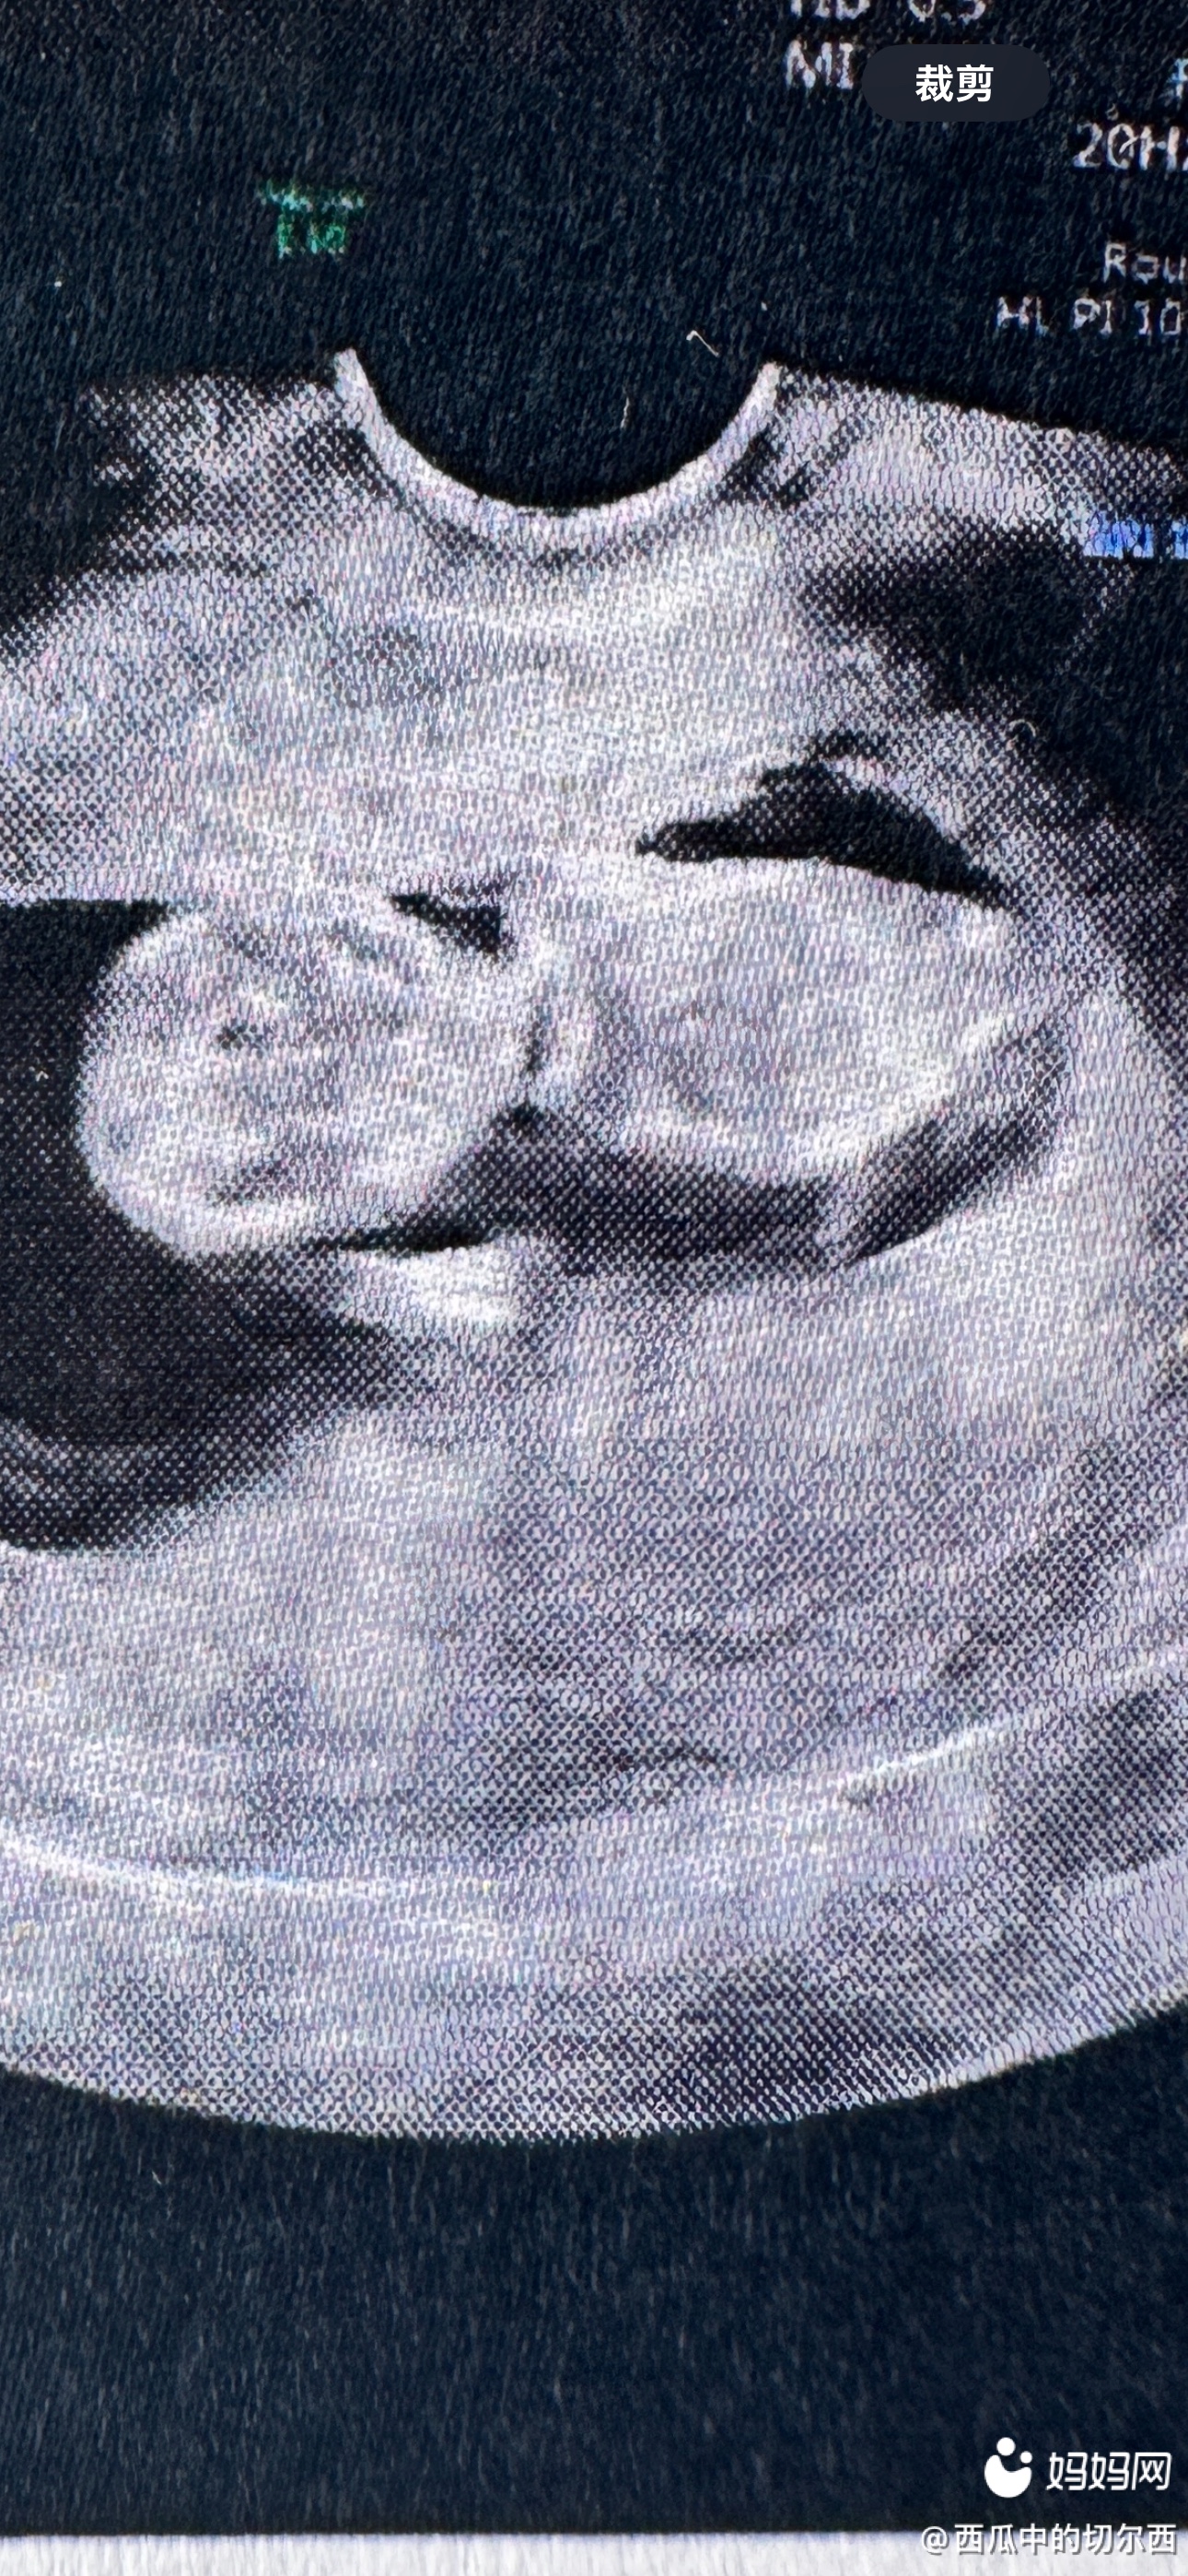

委屈怀孕刚开始不知道,等知道了11周了,之前一直都有干活,出摊收摊都是自己,我能忍,老公说他难受我忍,他干不了活,我忍,自己动手丰衣足食是我的宗旨,可是当我知道自己怀孕了我也没有闲着,还是该干嘛干嘛,现在14+2了,我还是自己出摊收摊,每天骑电瓶车20公里来回40公里,我忍,可是现在肚子出来了我担心路不平颠到宝宝,我门市上面有房子,每月都有交房租,我就想住这里,每次都是因为住这里我俩生气,他总爱发脾气,他名义上说怕我一人不安全,其实说白了就是怕我给他戴绿帽子,主要我现在一个孕妇我能出轨吗,就算出轨有人要吗,大肚婆谁敢惹,我不知道我应该怎么办,我是还和以前一样天天跑,还是住门市,住门市只会吵架,回家我担心孩子,左右为难